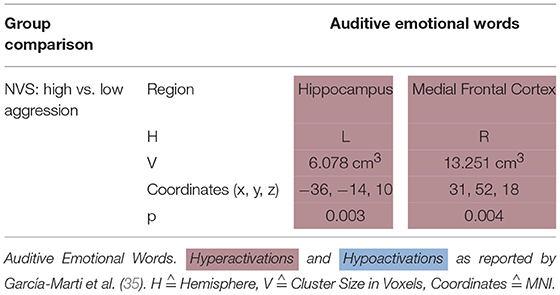

Emotional Words

García-Martí et al. (35) stimulated their subjects with auditive emotional words. In this paradigm, NVS with high aggression scores as opposed to those with low aggression scores hyperactivated the left hippocampus and the right medial frontal cortex (see Table 5D).

Auditive Emotional Words

Sanjuan et al. (70) used an auditory paradigm to induce emotion presenting schizophrenia patients and HC with neutral and emotional words. The authors used stimuli based on the most frequent words heard by psychotic patients with auditory hallucinations. When measuring activations by means of fMRI, patients as opposed to HC showed hyperactivity in the frontal lobe, temporal cortex, insula, cingulate, and amygdala.

García-Martí et al. (35) found that when hearing emotional words, high vs. low aggression violent persons with schizophrenia exhibited hyperactivation in the left hippocampus as well as in the right medial frontal cortex. The authors assume an association between the scale of aggression and certain brain regions responsible for cognitive and emotional processing. They hypothesize the alteration of neuronal circuits to favor a loss of empathic processes which could lead to aggressive behavior. These findings are partly in line with a study by Sanjuan et al. (70) where the authors found hyperactivity in the frontal lobe, temporal cortex, insula, cingulate, and amygdala when schizophrenia patients suffering from auditory hallucinations were confronted with emotional words. It remains unclear to which extent the findings by García-Martí et al. (35) are specific for violent behavior in schizophrenia.

Synthesis of Findings From Studies Using Emotion Induction Paradigms

When comparing high vs. low aggressive NVS in emotion induction paradigms (Figure 4D), authors reported hyperactivation in the right superior frontal gyrus and the left hippocampus. However, it remains unclear whether these activation patterns are specific for aggression.